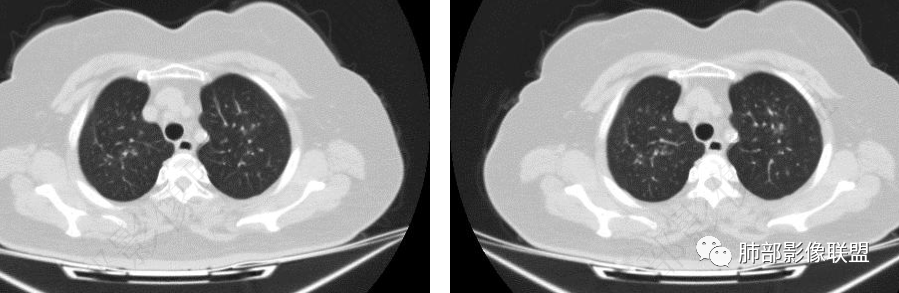

中老年女性,白细胞升高两年,实验室检查白细胞有所升高,双肺多发腺泡结节,边缘模糊,似乎支气管旁的血管增粗,但是斜裂没有增粗,所以不考虑肺水肿,病情变化快,2天后肺和肾衰竭,呼吸肌治疗,考虑血液病相关肺改变,ards早期病变。

支气管,弥漫增厚,及炎症,是像曲霉,不过白细胞三万有一点奇怪,也许需要后面随访ct看看

只能定到感染,进展如此迅速,2天上机,3天肾替代,不知道是啥

确实。这个人好奇怪,白细胞这么高,淋巴比例高,但T细胞亚群低。这个人有没有血液系统的问题呢?这个支气管镜也很有意思,符不符合曲霉呢…比较轻的曲霉菌感染,可以很表浅,有黏膜充血等,没有看到他描述假膜之类的。中性粒,白细胞,降钙素,C反应蛋白都是升高的。支持存在感染,细菌在前吧?斗胆猜一下,除实验室外,腺泡结节为主,累及支气管壁,支气管肺炎的表现,病程较长,未见明确肉芽肿形成,真菌的可能性偏低,猜化脓菌在前,建议进一步排查合并血液系统疾病。

老年女性,发现白细胞升高两年,此次入院多次查外周血白细胞>30*10^9/L,淋巴降低,CRP显著升高,但病程中无发热,以细菌性炎不好解释;CT提示有脾大,结合外周血象,首先考虑存在血液系统疾病(白血病)基础,且未系统诊治;肺部CT提示双肺中轴间质增粗,伴随支气管管壁增厚?多发树丫及腺泡结节,部分呈点晕征,可见肺动脉分枝增粗,一元论考虑白血病肺部浸润;二院论考虑白血病并发气道侵袭曲霉。以患者病程进展看,更倾向于白血病肺部浸润。

白细胞啥意义?正常不应该4~10,这么高有啥提示?

急性化脓性感染?白血病?